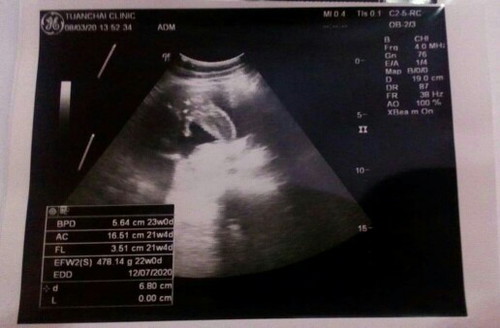

เมื่อวันอาทิตย์ไปหาคุณหมอมา หมอบอกว่าน้องตัวเล็กน้ำหนักน้อย ตอนนี้ 22 สัปดาห์แล้วแต่ 400 กว่ากรัมเอง!! แต่น้องดิ้นเก่งมาก คือดิ้นทั้งวันยิ่งช่วงกลางคืนดิ้นแรงมากค่ะ มีผลอะไรเกี่ยวกันมั้ยคะ...? ทำไงดีคะ...? กลัวจะมีผลตอนคลอดจัง...